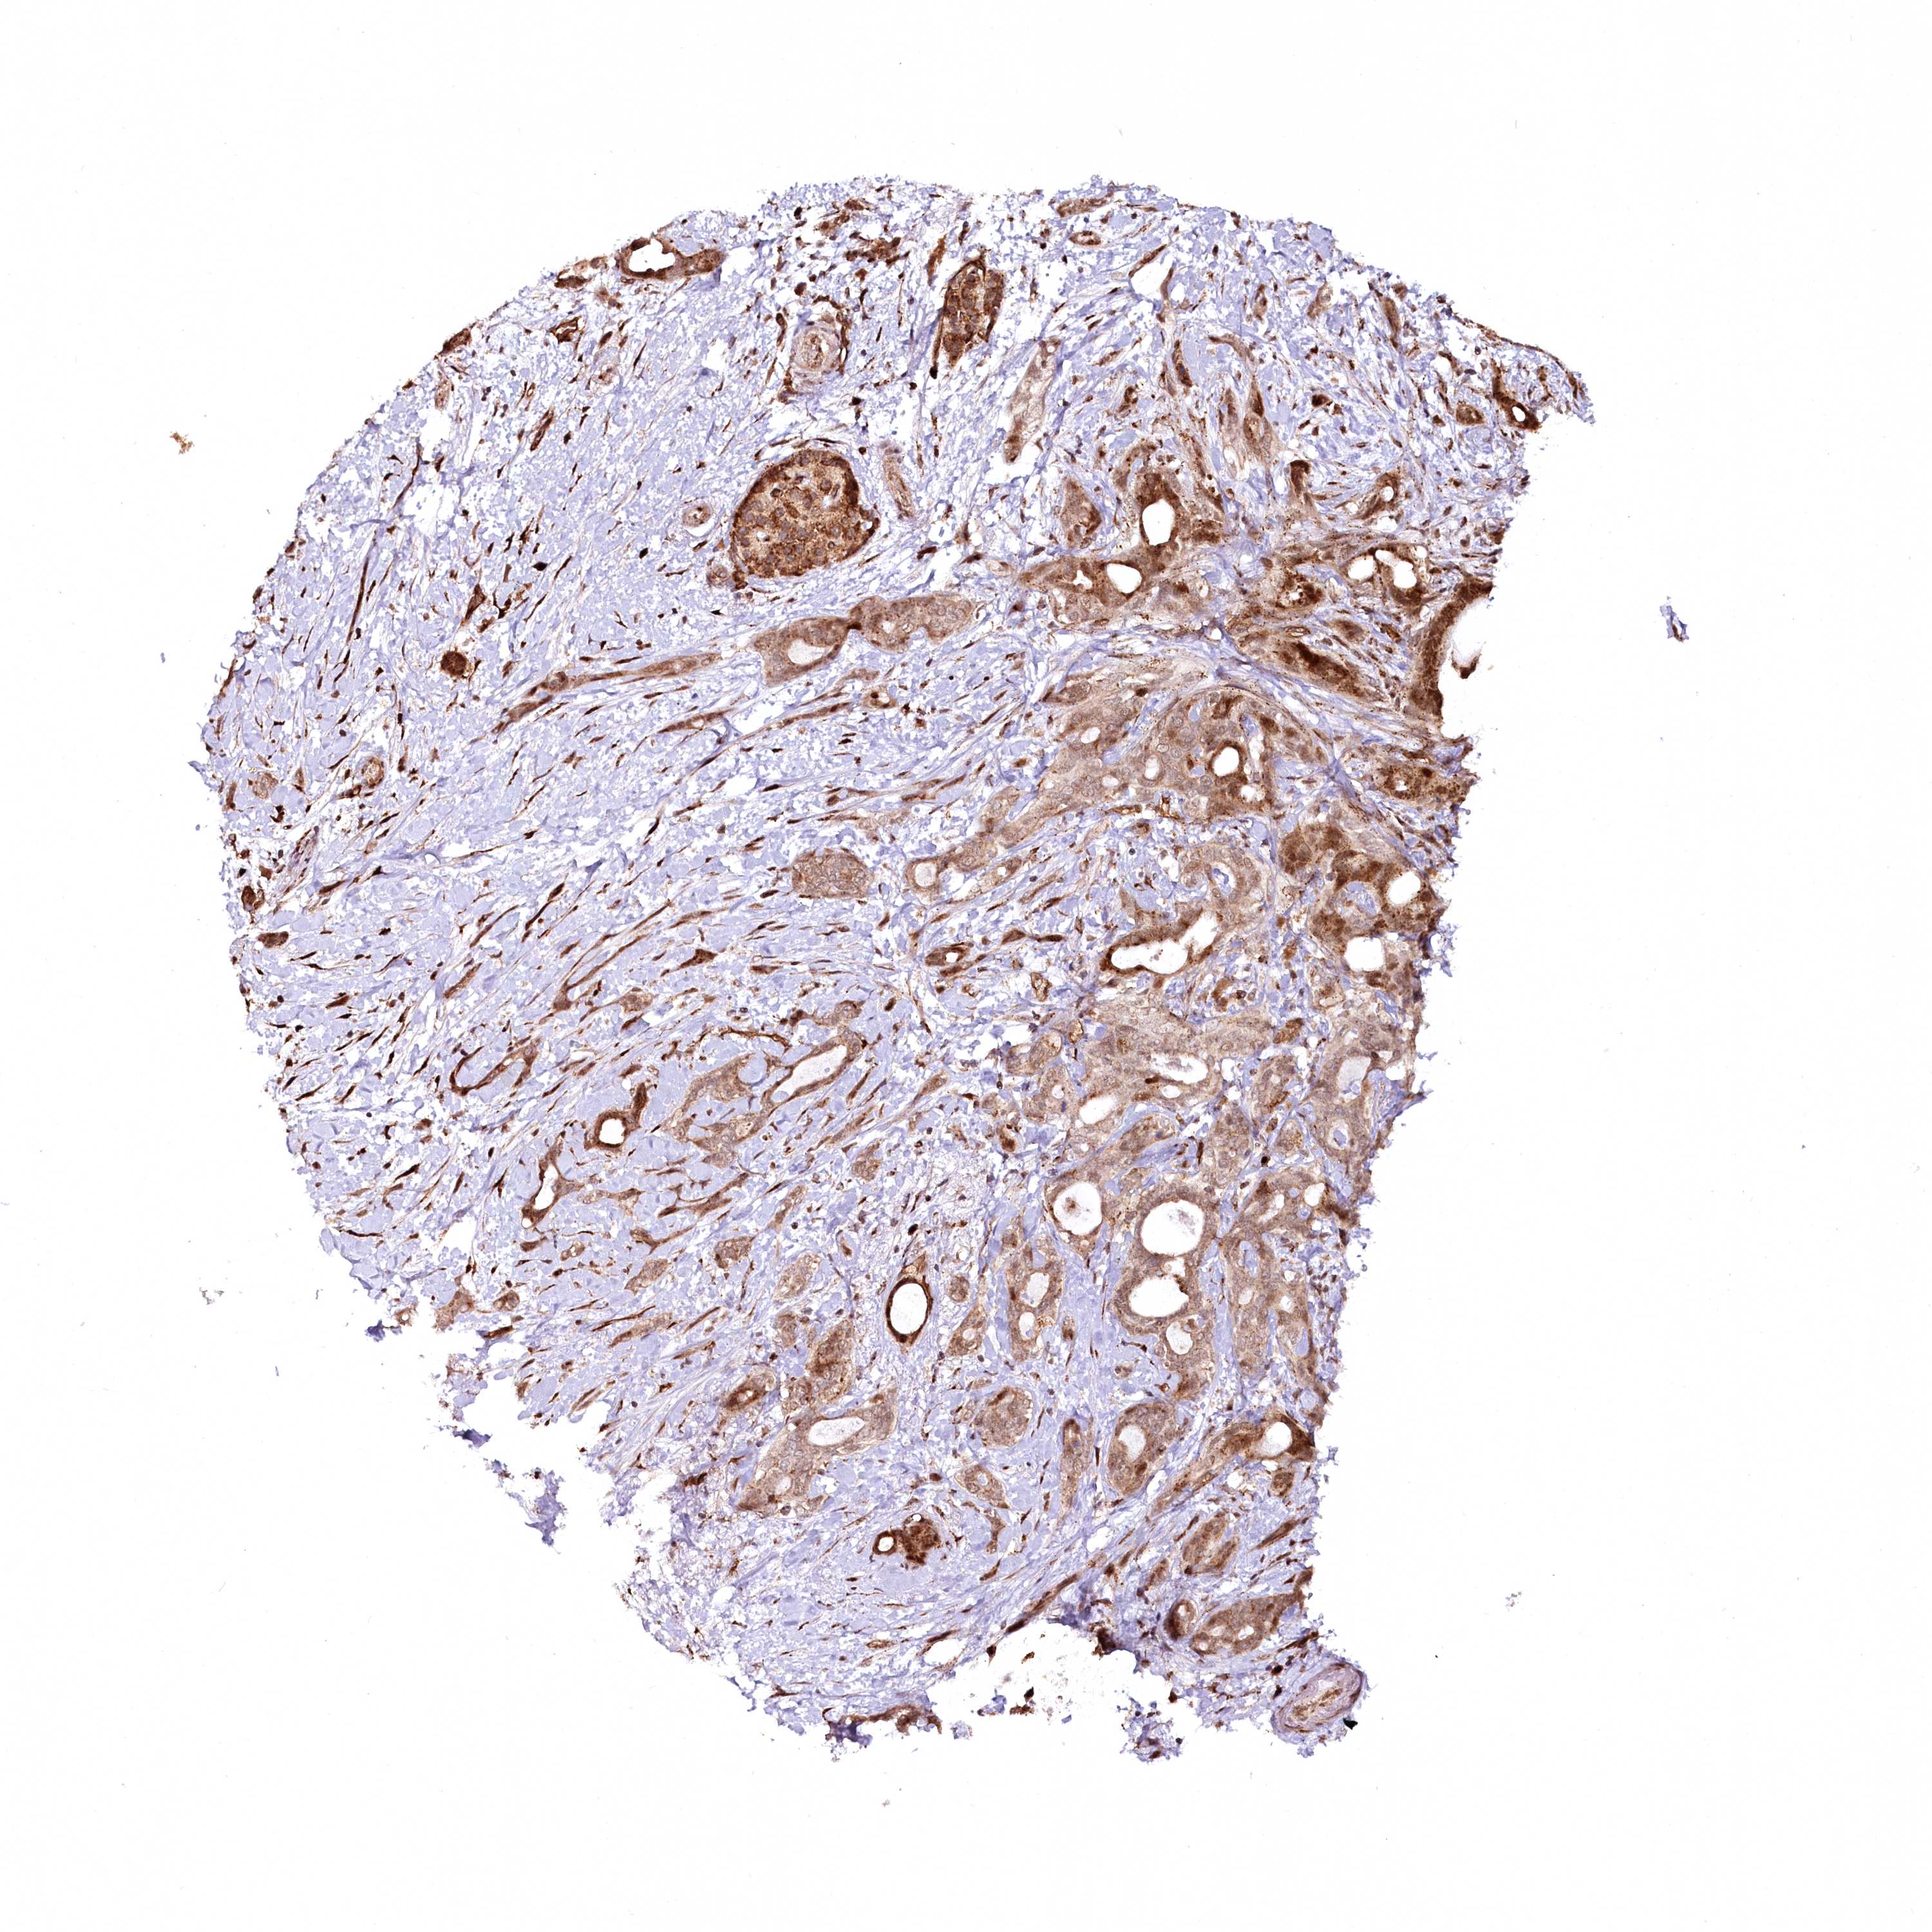

PANCREATIC CANCER - Protein expressioni

A mouse-over function shows sample information and annotation data. Click on an image to view it in a full screen mode. Samples can be filtered based on level of antibody staining by selecting one or several of the following categories: high, medium, low and not detected. The assay and annotation is described here.

Note that samples used for immunohistochemistry by the Human Protein Atlas do not correspond to samples in the TCGA dataset.

Antibody stainingi

Antibody staining in the annotated cell types in the current human tissue is reported as not detected, low, medium, or high, based on conventional immunohistochemistry profiling in selected tissues. This score is based on the combination of the staining intensity and fraction of stained cells.

Each image is clickable and will lead to virtual microscopy that enables deeper exploration of all samples and also displays staining intensity scores, fraction scores and subcellular localization as well as patient and tissue information for each sample.

Antibody HPA037866

Antibody HPA037867

Antibody HPA045712

Staining

High

Medium

Low

Not detected

Intensity

Strong

Moderate

Weak

Negative

Quantity

>75%

75%-25%

<25%

None

Location

Nuclear

Cytoplasmic/membranous

Cytoplasmic/membranous,nuclear

Adenocarcinoma, NOS